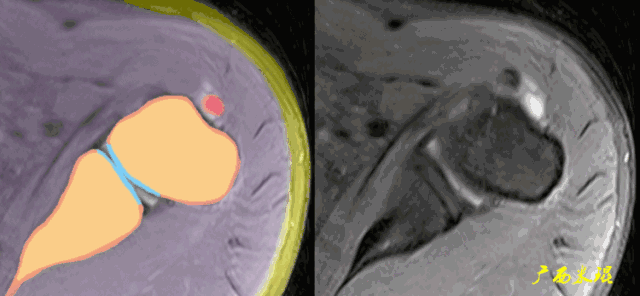

1、斜冠状位:平行于冈上肌腱长轴,主要评估冈上肌。

各个序列肩袖均表现为均匀的低信号,是肌腱的延续。